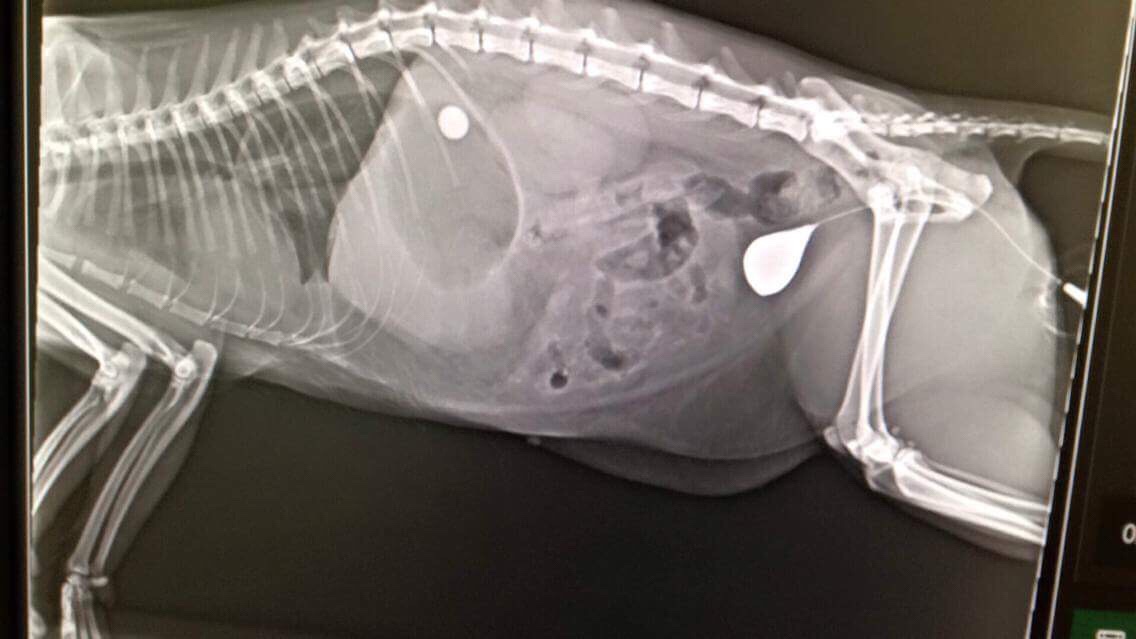

– Nééézd!

– Ez miiiii?

– Most vittem be a kontrasztanyagot. Hát nem csodaszép?